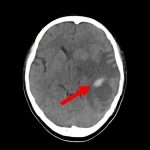

断層撮影

手術前1